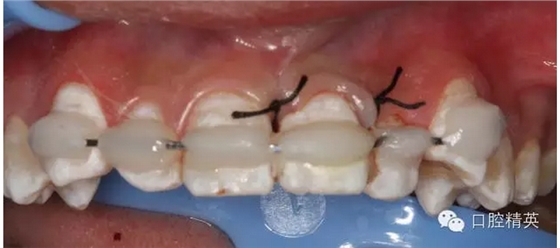

圖1.術(shù)前患者口內(nèi)像、牙槽窩輕度收縮、血凝塊穩(wěn)定、無滲出。

圖2.口內(nèi)整體影像